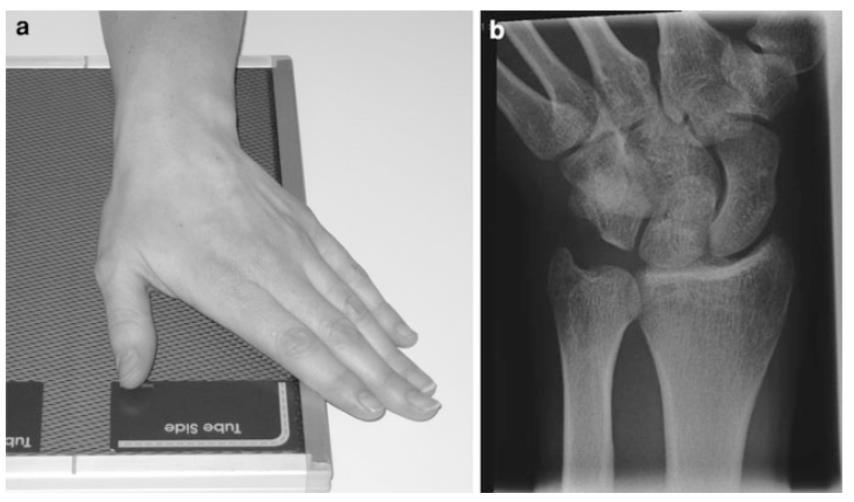

15. Anatomía radiológica del carpo

Marcela Pérez Muñoz, Camilo González Gómez…………….…………………………..